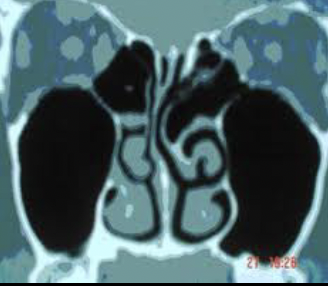

IMAGEN OCUPACIÓN DE 95% HEMOGÉNEA SENO MAXILAR

OTRO SENO IMAGEN DE OCUPACIÓN 60%

LOS SENOS ETMOIDALES TAMBIÉN ALTERADOS. SEPTUM DESVIADO EN LA DERECHA.

PALADAR ASIMÉTRICO: DATOS DE RESPIRADOR BUCAL CRÓNCO